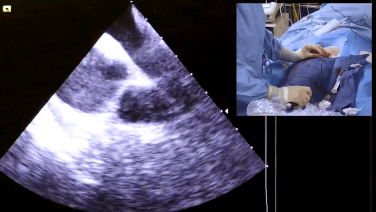

Intracardiac Echo Views During the AF Procedure with Brett Gidney, MD

Obtaining ICE Views to Visualize Atrial Anatomy with Joshua Silverstein, MD